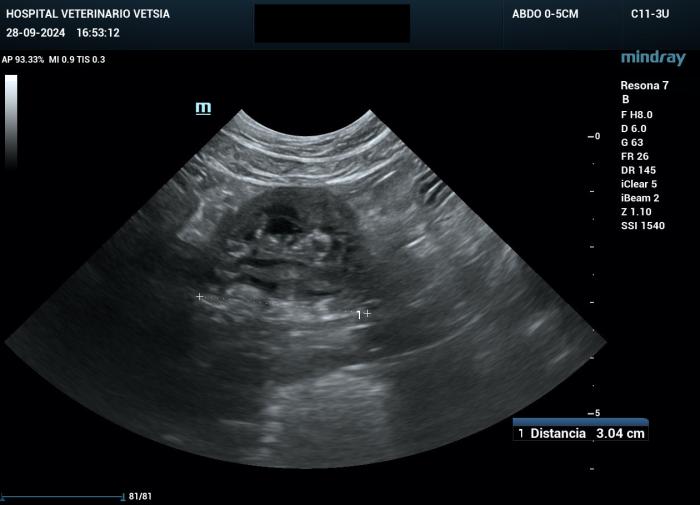

La ecografía abdominal evidenció un engrosamiento moderado de la mucosa y de la submucosa, y leve de la capa muscular del yeyuno y del íleon, generando un efecto masa transmural (Figura 2A-B).

Figura 2A-B. Imágenes ecográficas en las que se aprecia un engrosamiento de la mucosa y submucosa yeyunal, con alteración asimétrica de la capa muscular.

La grasa mesentérica adyacente se mostró moderadamente hiperecogénica, y se identificó una escasa cantidad de líquido libre, insuficiente para toma de muestra.